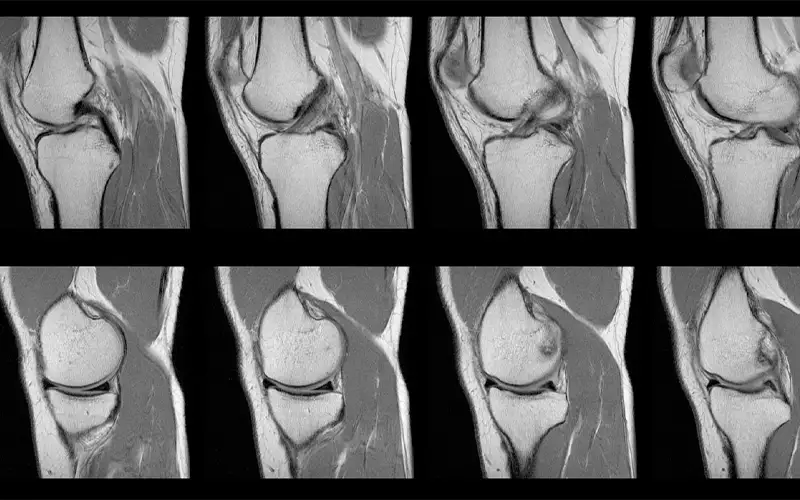

نقش MRI در تشخیص آسیبهای منیسک

امروزه MRI بهعنوان روش استاندارد و غیرتهاجمی برای تشخیص آسیبهای منیسک در نظر گرفته میشو...